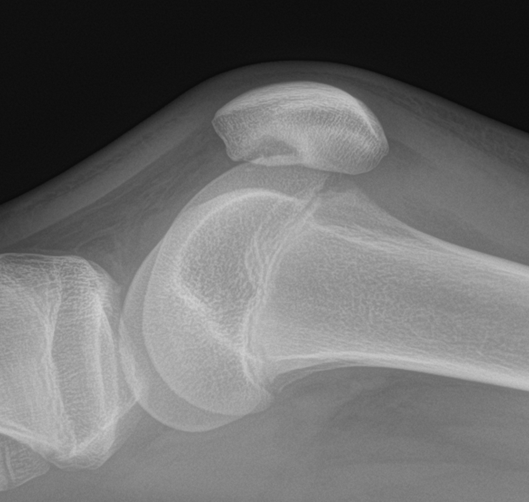

One of the critical areas requiring development is the ability to cater to high-level athletes. This includes the need for advanced sports medicine facilities and clinicians to identify, manage, and treat injuries such as muscle injuries, tendon related conditions, ligament tears and joint conditions. The success of events like the World Cup will depend heavily on the availability of skilled professionals and robust medical infrastructure.

We’re proud to be featured in the British Journal of Sports Medicine as the #1 most-read BJSM Blog of 2024. Our work on meniscus tears, repair strategies, and rehabilitation options was recognized as a leading resource for preserving tissue function and guiding clinical pathways.